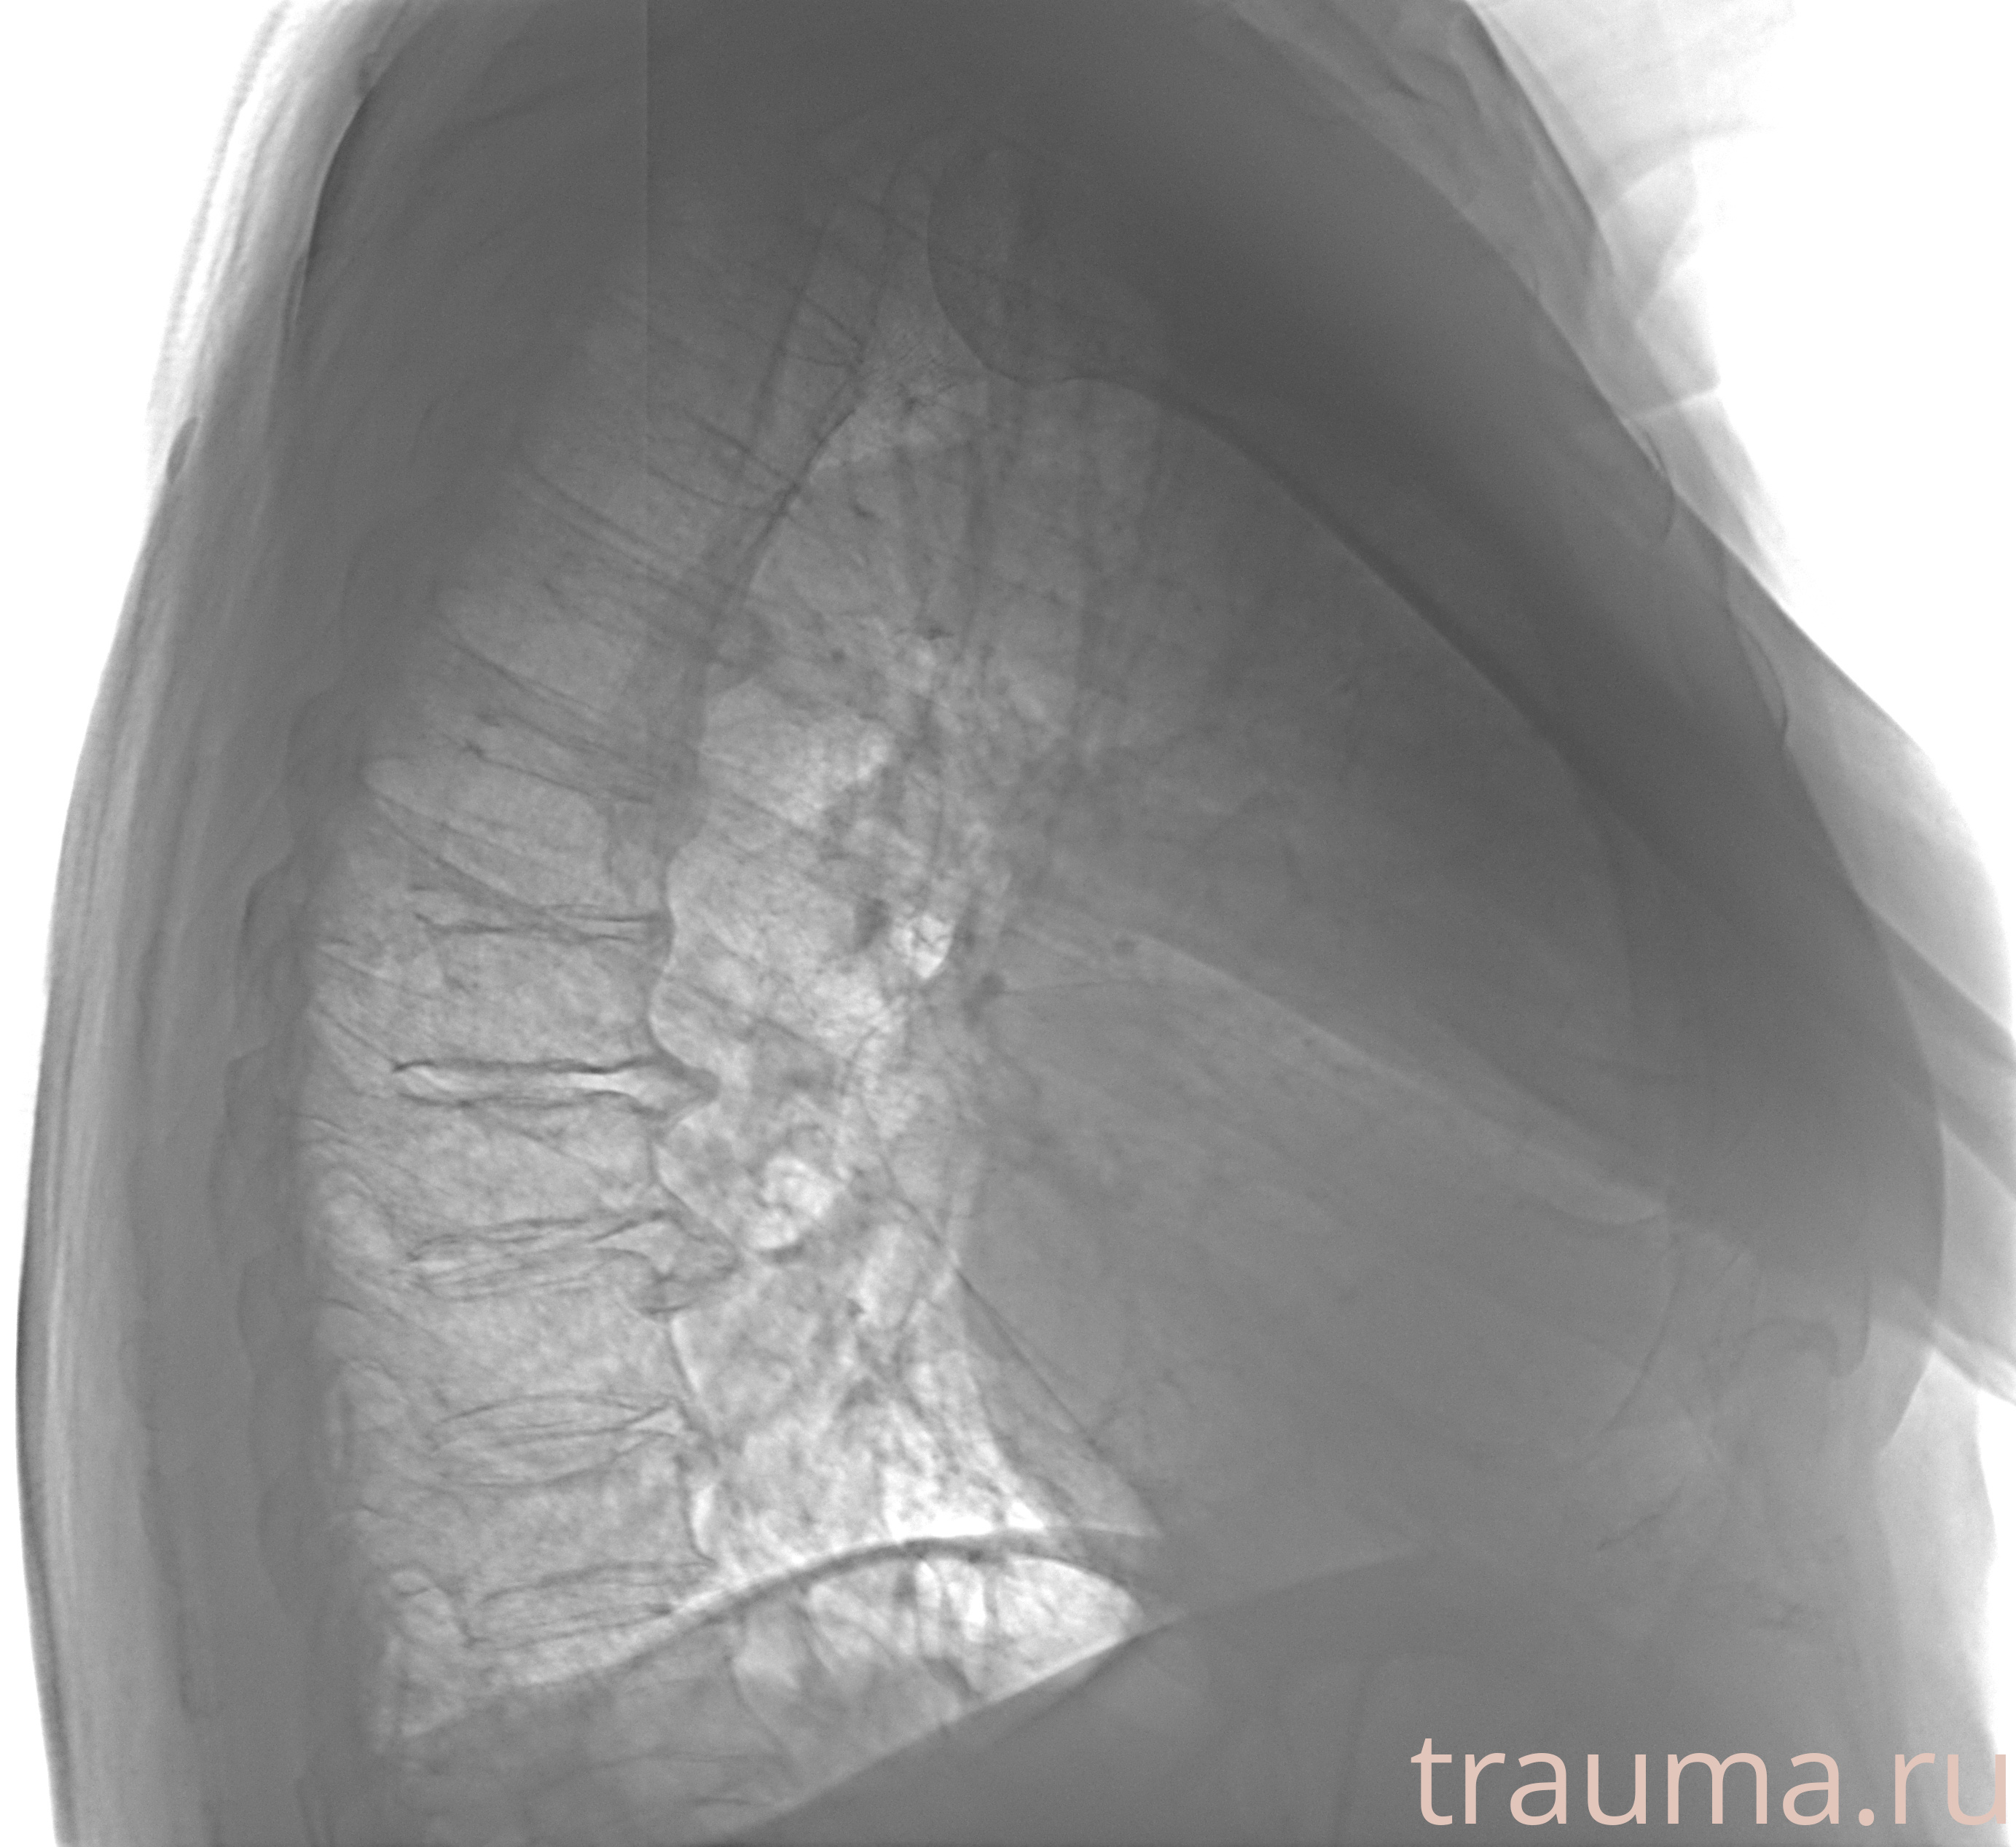

Рентген на дому: по вашему адресу приезжает врач-рентгенолог, травматолог-ортопед с мобильным рентгеновским аппаратом, проводит диагностику травмы или заболевания, делает необходимые рентгенограммы, дает рекомендации по дальнейшему лечению. Получить качественные снимки в домашних условиях возможно благодаря уникальной методике, разработанной МосРентген Центром для института  Склифосовского